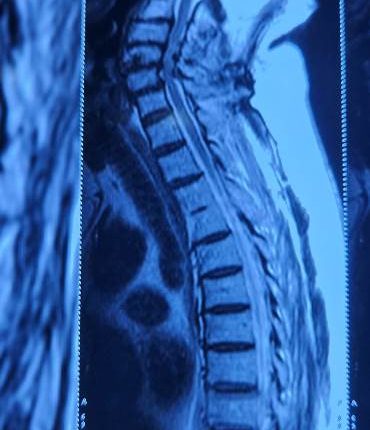

Mumbai: A 71-year-old male patient from Malad (Mumbai) underwent a successful posterior cervical laminectomy for multilevel cervical spondylotic myelopathy at Apex Hospital, Borivali which is part of Apex group of Hospitals last week. The surgery marked another important milestone in the hospital’s commitment to advanced spine care. The patient had been experiencing gait instability, weak hand grip, difficulty with fine motor tasks like buttoning his shirt, and radiating pain in both upper limbs—classic symptoms of cervical myelopathy, a condition caused by compression of the spinal cord in the neck due to age-related degenerative changes. If left untreated, this condition can progressively impair mobility and hand function, significantly diminishing quality of life. Following a comprehensive clinical evaluation and imaging, the diagnosis of multilevel cervical myelopathy was confirmed. The surgical team opted for a posterior cervical laminectomy, a procedure designed to relieve pressure on the spinal cord by removing the compressive bony structures. The surgery was performed by Dr. Umang Sheth and Dr. Meet Shah, Spine Surgeons at Apex Hospital, Borivali. The procedure lasted 2 hours and 15 minutes, with minimal blood loss (approx. 100 ml) and no intraoperative complications, ensuring a smooth and safe operative course.